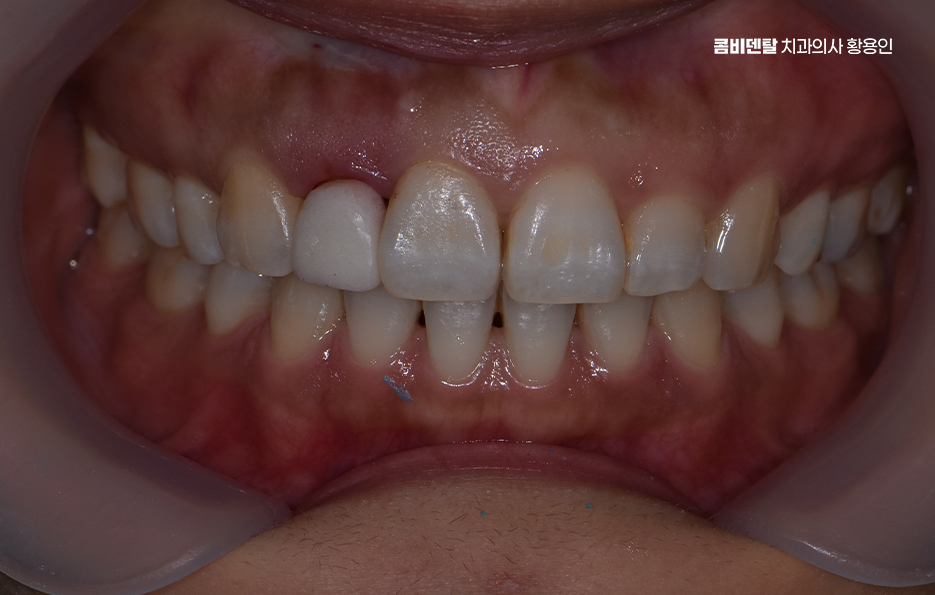

앞니 올세라믹 마지막 단계는 완성된 올세라믹 크라운을 치아에 접착하고, 교합을 조정하는 마무리 단계로 이때 중요한 건 주변 치아와 얼마나 조화롭게 어우러지는지를 보는 거예요. 색상은 단순히 ‘흰색’ 하나로 결정되는 게 아니라, 투명도, 밝기, 색조까지 섬세하게 조정돼야 하고 특히 앞니는 음식을 자르거나 말할 때 중요한 기능을 하기 때문에, 교합, 즉 맞물림이 정확해야 장기간 사용할 수 있어요.

앞니에 크라운 치료를 할 때는 주로 올세라믹 크라운을 심미적인 이유로 사용하지만 앞니의 손상이 심해서 잔존 치아가 많지 않은 경우에는 지르코니아 크라운을 사용하여 좀더 내구성에 초점을 두는 경우도 있는데 요즘은 올세라믹과 지르코니아의 장점을 합친 하이브리드 올세라믹 크라운도 많이 쓰이고 있기 때문에 자신에게 적합한 치료 방법에 대해서는 경험 많은 치과의사와 먼저 충분히 상의하시길 바라고 있었어요

특히 앞니 치료 후에는 관리도 더욱 중요한데 올세라믹은 변색이나 부식에는 강하지만, 강한 충격에는 약할 수 있어서 앞니로 딱딱한 음식을 깨물거나, 병뚜껑을 따거나, 이를 악무는 습관이 있다면 주의가 필요하고 정기적인 스케일링과 검진을 통해 보철물 주변 잇몸 상태 또한 체크하는 것도 필수라고 할 거예요

올세라믹 치료는 심미성과 기능성을 동시에 고려해야 하는 정밀 치료이기 때문에 치료 자체도 무척이나 중요하겠지만 금과 같은 금속 재질의 보철물과는 달리 앞니이기 때문에 깨질 수 있는 보철물의 특성을 잘 고려하여 장기적인 보철물의 유지 관리가 곧 자연치아의 수명과도 직결된다는 점을 꼭 이해하시고 향후 관리까지 치료 후 지속성까지 고려한 치료 계획을 잘 세우시길 바라고 있어요